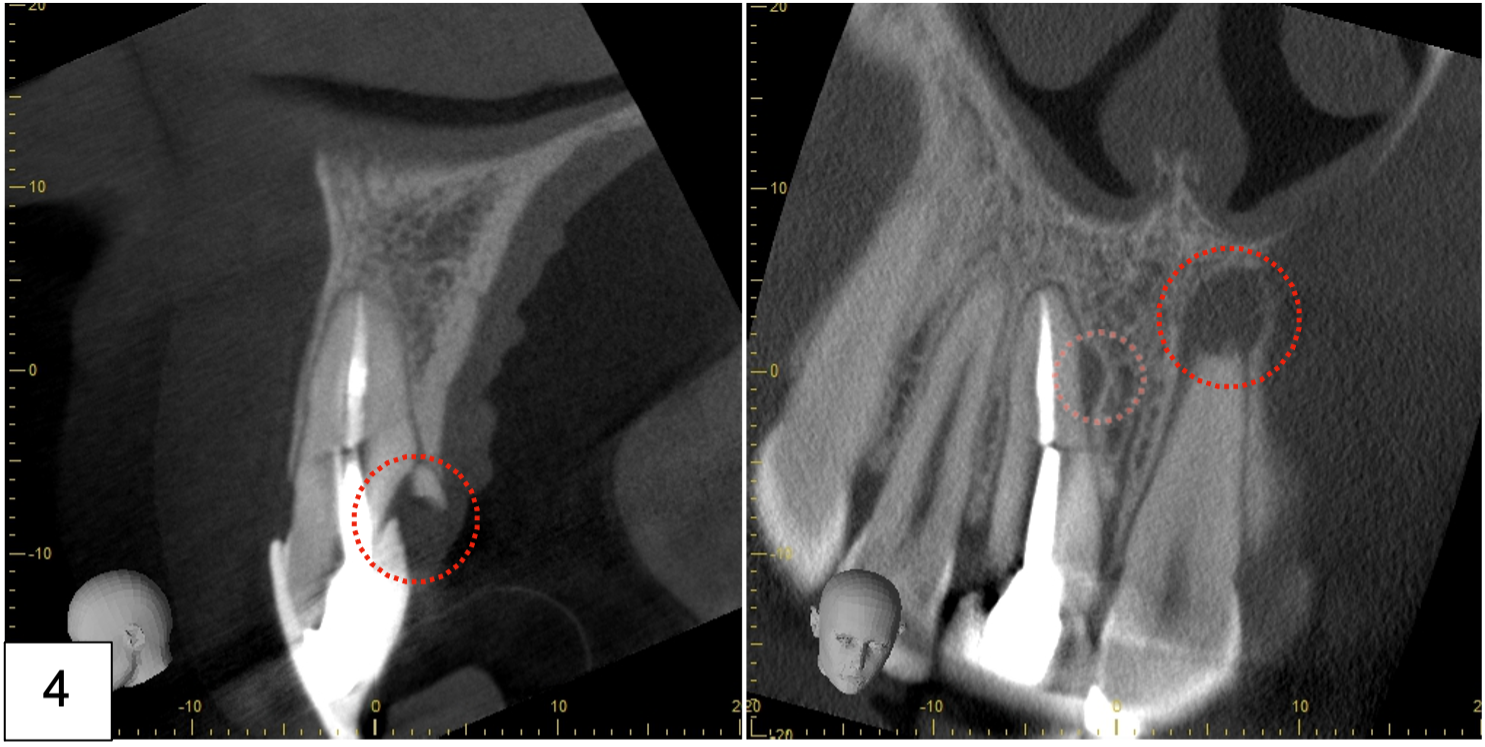

• Bilan 3D ou Tomographie volumique à faisceau conique ou Cone Beam Computed Tomography (Photo 4)

Sur le cone beam réalisé nous retrouvons bien notre lésion latérale au niveau de 11 et notre lésion apicale au niveau de 21. A noter également la fracture palatine du tiers cervical radiculaire.

On note la présence d’une paroi osseuse vestibulaire intacte permettant d’envisager une extraction

atraumatique suivie d’une implantation immédiate, dans de bonnes conditions.